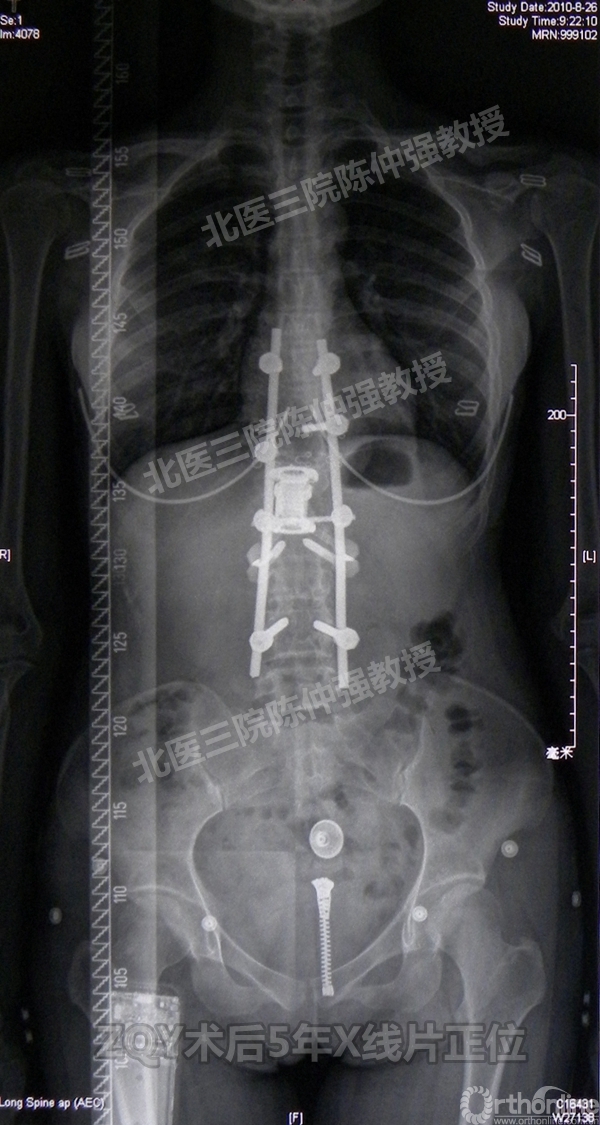

ZQY术后5年

患者女性17岁,胸腰椎陈旧结核性侧后凸畸形,局部呈“麻花状”扭转,无神经功能受损表现。2005年,陈仲强教授带领团队实施后路+侧前方联合入路脊柱节段切除、双轴旋转矫形术。术后患者外观显著改善,神经功能正常。术后随访证实患者截骨矫形节段骨性融合良好,矫形效果持续良好。